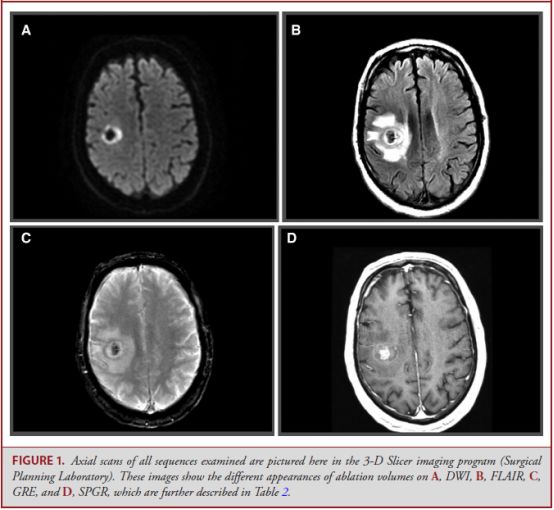

背景:MRI引导下激光间质热疗(MRgLITT)是一种新型、微创的方法,现今被广泛用于颅内各种病理性疾病。本文探讨了经过MRgLITT治疗的患者,在估算消融体积时,选择何种MRI序列能够提供最高的可信度和最小的变异率。

研究选取了20例经过MRI引导下激光热疗的患者,3位评测者随后使用MRI的不同序列:毁损梯度回波序列(SPGR),FLAIR序列,弥散加权序列(DWI),及梯度回波序列(GRE)。测量的结果使用组间相关分析来确定3位测评者的一致性。

结果:SPGR序列具有最高的一致性,组间关系0.981,其次为DWI序列,组间关系为0.958,一致性最低的为GRE序列(0.895)和FLAIR序列(0.866)。与其他序列相比,SPGR还具有最小的变异率和一致性最高的体积。

基于该研究结果,作者认为,SPGR序列在评估MRgLITT后病变区域的一致性方面占据最高地位,而对于不能做增强MRI的患者,DWI序列可以作为相对可靠的次选项目。